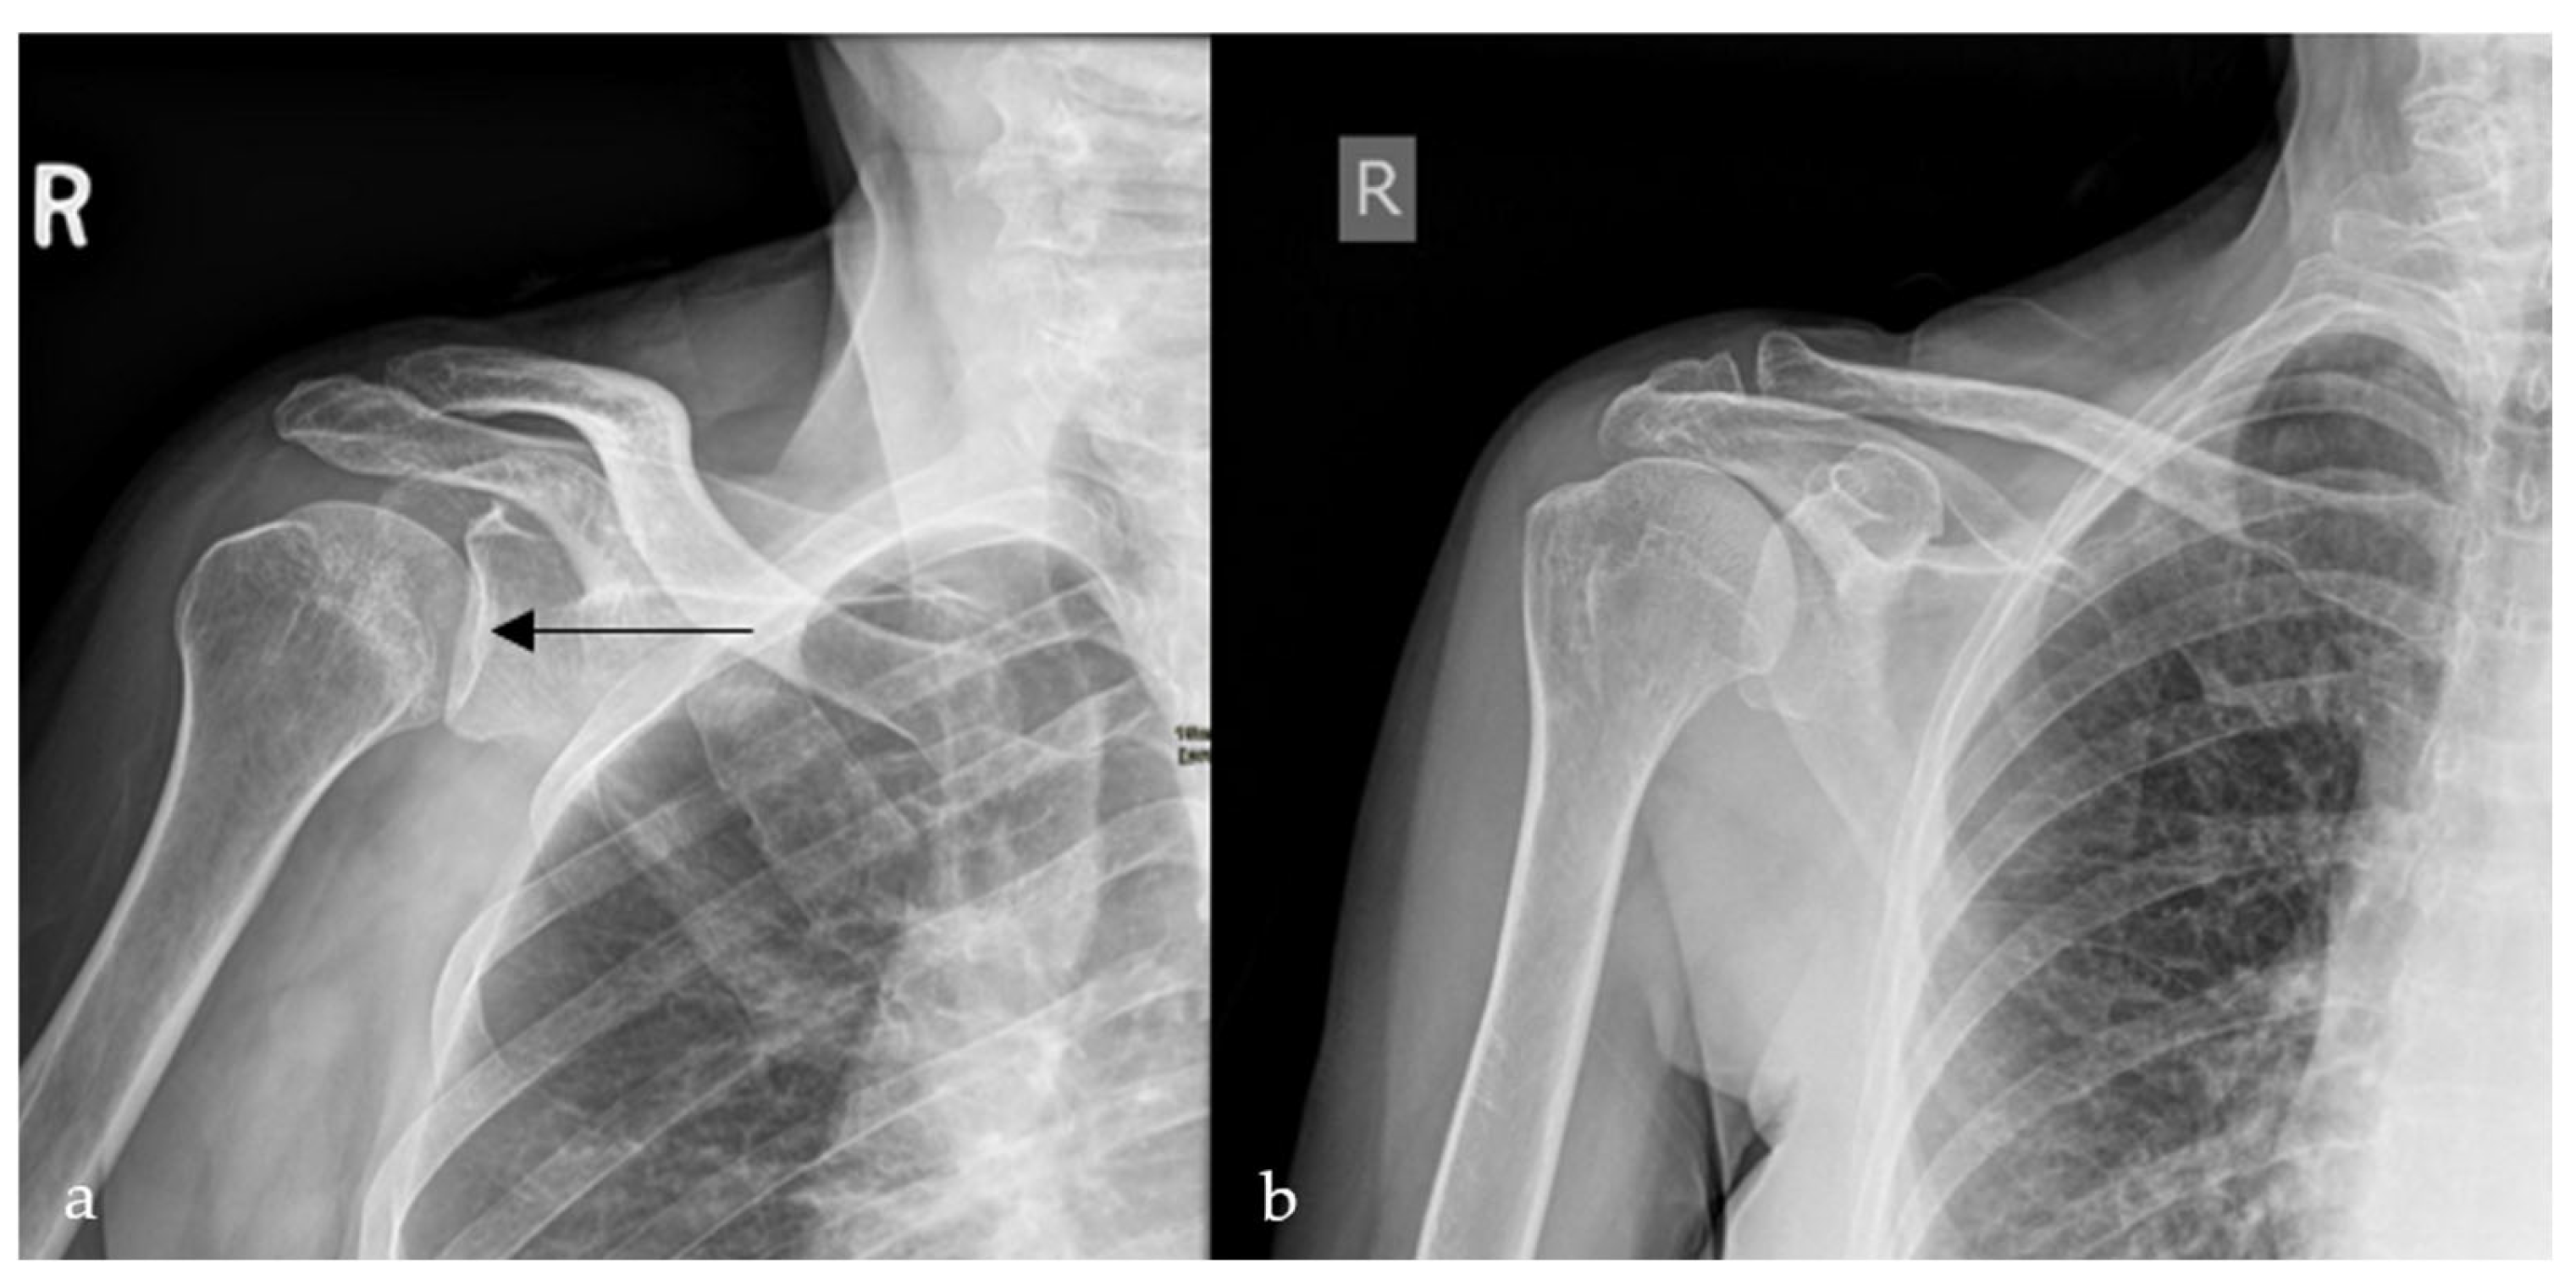

2.4. Loss of Half-Moon Overlap Sign